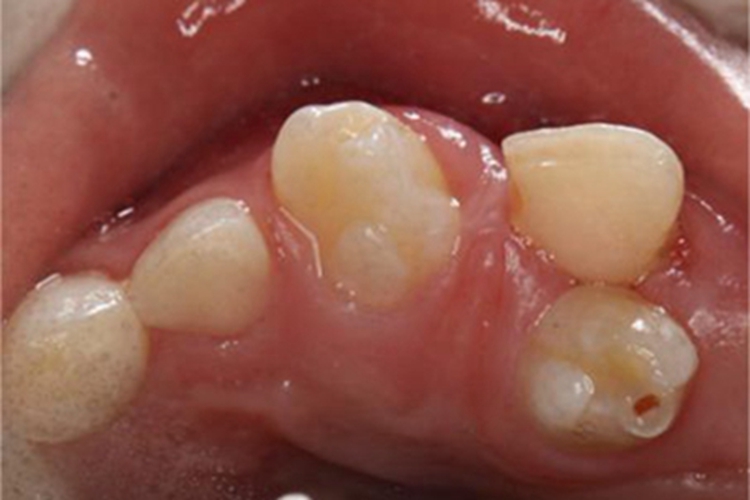

多生牙的生长一般无确切时间,表现为口腔内有多余的牙齿出现,形态变异较大,可呈圆锥形、结节形,或是与正常牙齿形态相似。由于多生牙占据了牙弓间隙,使正常恒牙萌出受影响,容易导致牙列拥挤、牙间隙大等情况,最终出现畸形。